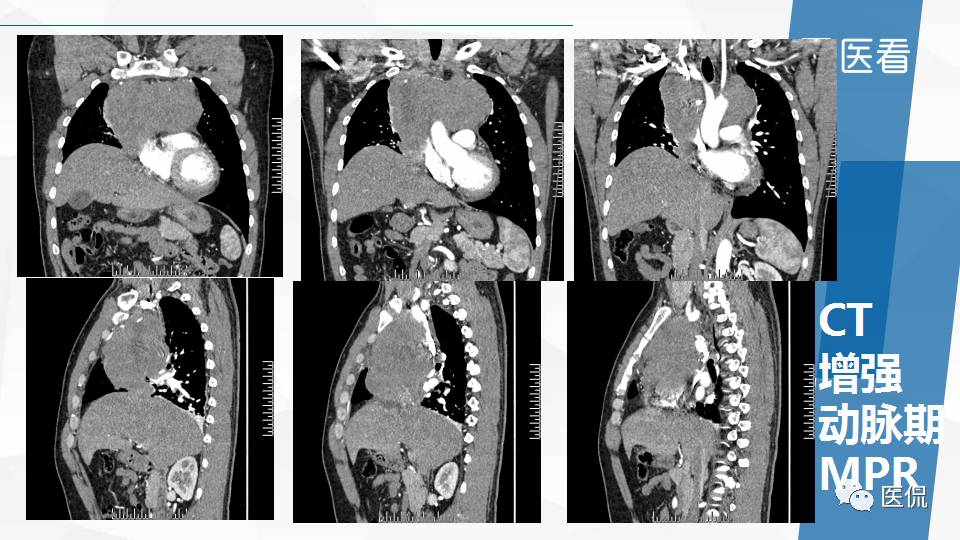

纵隔精原细胞瘤案例 (精原细胞瘤影像表现与鉴别诊断)

精原细胞瘤ct影像,精原细胞瘤影像特征